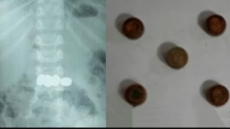

മേപ്പാടിയില്‍ രണ്ട് വയസ്സുകാരന്‍ വിഴുങ്ങിയ അഞ്ച് ബാറ്ററികള്‍ എന്‍ഡോസ്‌കോപ്പിയിലൂടെ പുറത്തെടുത്തു

മേപ്പാടി: കളിപ്പാട്ടത്തിലുണ്ടായിരുന്ന അഞ്ച് കോയിന്‍ ടൈപ്പ് ബാറ്ററികള്‍ വിഴുങ്ങിയ രണ്ട് വയസ്സുകാരനെ എന്‍ഡോസ്‌കോപ്പിയിലൂടെ വിജയകരമായി രക്ഷപ്പെടുത്തി. ബത്തേരി മൂലങ്കാവ് സ്വദേശികളുടെ മകനാണ് അപകടത്തില്‍പ്പെട്ടത്.

- കുട്ടി ബാറ്ററികള്‍ വിഴുങ്ങുന്നത് കണ്ടതോടെ വീട്ടുകാര്‍ ഉടന്‍ ആശുപത്രിയില്‍ എത്തിച്ചു.

- ഡോ. മൂപ്പന്‍സ് മെഡിക്കല്‍ കോളജിലെ ഗാസ്‌ട്രോ എന്ററോളജി വിഭാഗം സ്‌പെഷലിസ്റ്റ് ഡോ. സൂര്യനാരായണയുടെ നേതൃത്വത്തിലായിരുന്നു എന്‍ഡോസ്‌കോപ്പി വഴി ബാറ്ററികള്‍ പുറത്തെടുത്തത്.

- സമയബന്ധിതമായ ചികിത്സ ഉറപ്പാക്കാനായതിനാല്‍ വലിയ അപകടം